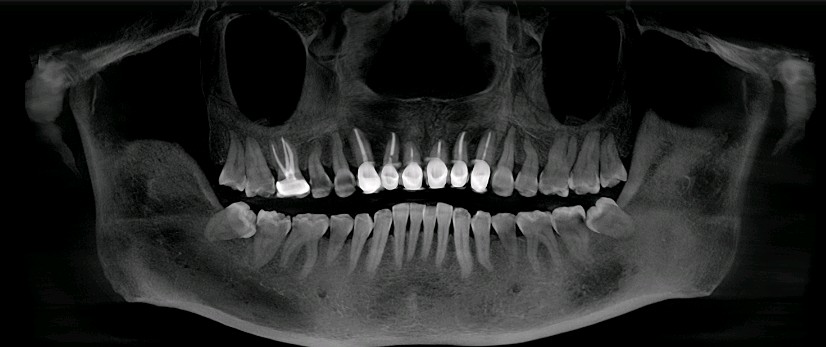

人的口腔内最少有28颗牙齿,多则有32颗。多的这是颗就是智齿。也是牙弓的最后一颗。

那么一般什么样的智齿需要拔除呢?1、阻生齿或和相邻磨牙接触不正常的智齿。2、咬腮智齿3、对颌没有牙,没有咬合功能的智齿。4、智齿本身存在牙体疾病。

对于以上这些智齿如果不拔除会有哪些危害呢?1、会顶坏邻近牙齿。常常塞牙导致邻牙龋坏或者牙槽骨吸收。2、容易引起智齿冠周炎。智齿萌出不全异位或者阻生。牙龈与牙体之间容易形成一个狭窄较深的盲袋。易积攒食物残渣滋生细菌。时间长了就会造成智齿冠周炎起疼痛,肿胀,张口受限,严重了会导致间隙感染。3、影响咬合。智齿萌出位置异常,导致咬合关系错乱,影响颞下颌关节的正常活动。4、位置靠后不易清洁,食物残渣堆积容易发生龋坏,长期以往会发展成牙髓炎,发生疼痛的现象。